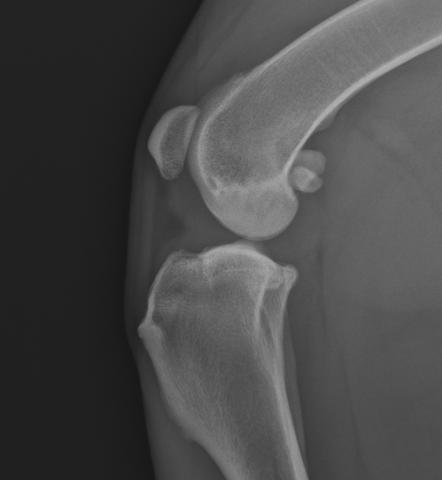

Luxace čéšky a přetržení předního zkříženého vazu – častá příčina bolavého kolene starších psů

Luxace čéšky (pately) je jednou z nejčastějších vrozených vývojových vad pohybového aparátu psů. Vede k rozvoji artrózy v koleni a díky dlouhodobé nestabilitě kloubu později nezřídka také k přetržení předního zkříženého vazu.